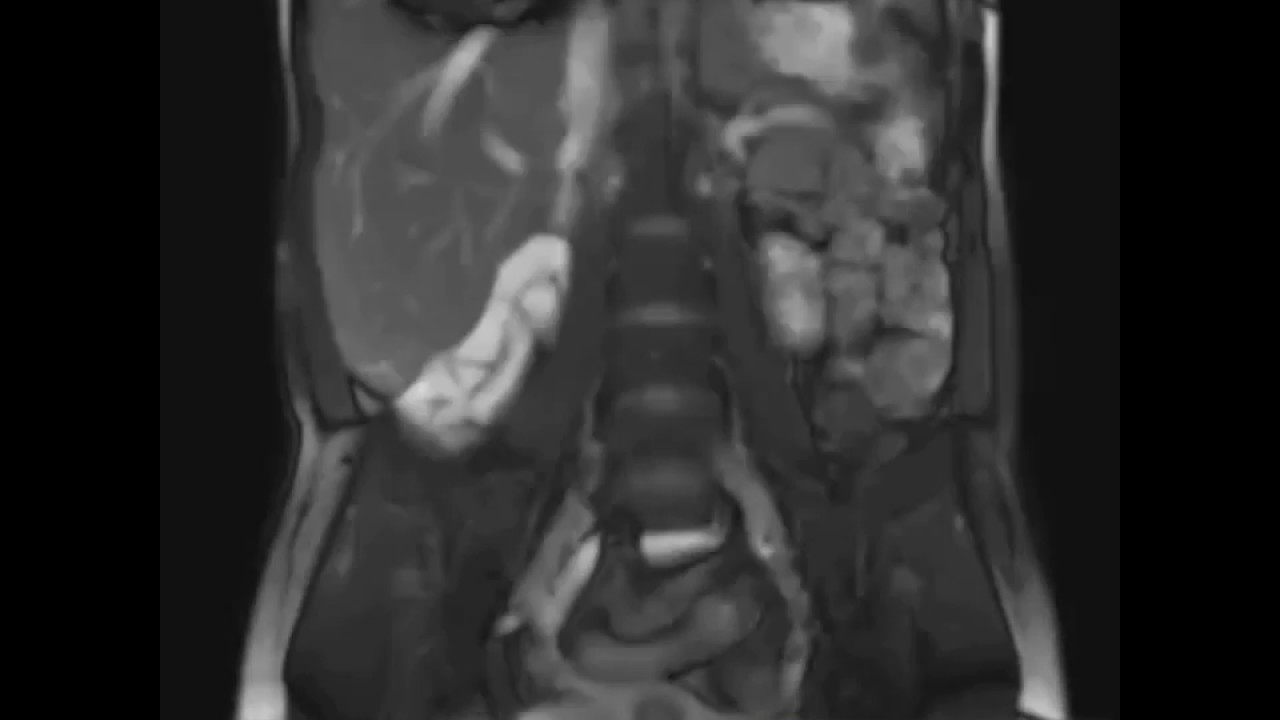

а-с Болезнь Крона. МР-ирригография. Длинный сегмент утолщенной кишечной стенки хорошо визуализируется в корональной проекции на Т2- (а) и Т1-взвешенных изображениях (b).

После внутривенного введения контраста (с) утолщенная стенка петли терминального отдела подвздошной кишки резко усиливается, что является индикатором пика воспалительного процесса.